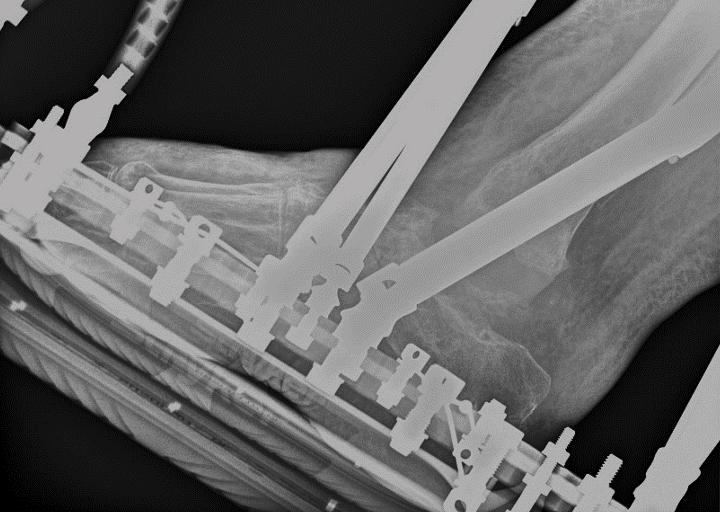

At this point, we used computer-generated hexapod external fixation technology. We applied a circular frame to realign the ankle joint by soft tissue distraction utilizing olive pins in the tibia, calcaneus, and metatarsals. It took 6 weeks to attain a corrected position (see first and second photos to left). Also, complete restoration of the joint space allowed restoration of the talar body. We also noted that the distraction process reduced the bulk of the lateral flap.